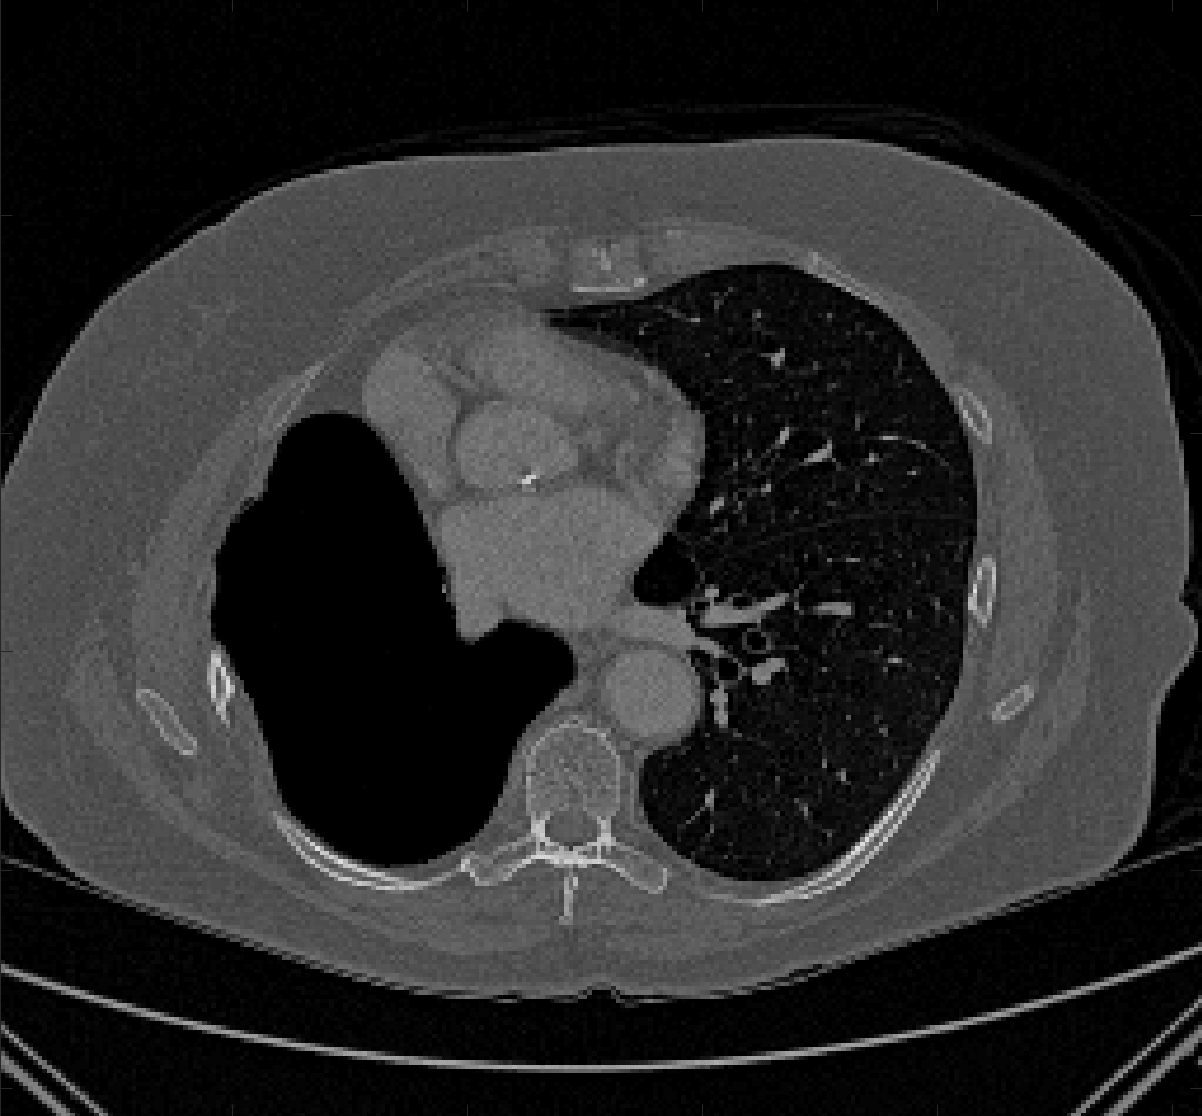

Test Images. We will perform initial tests on the images shown in Figs. 5–7. We have provided the ground truth and initialisation used for each image. Test Images 1–3 are synthetic, Test Image 4 is an MRI scan of a knee, Test Images 5–6 are abdominal CT scans, and Test Images 7–9 are lung CT scans. They have been selected to present challenges relevant to the discussion in §2. We focus on medical images as this is the application of most interest to our work. In the following we will discuss the results in terms of synthetic images (1–3) and real images (4–9). We also test the proposed approach on a larger data set of 30 CT images (a sample of which is presented in Fig. 18), comparing against existing selective methods detailed in §3.

Real Images. In Table 1 we can see that the proposed model is the most successful in terms of optimal accuracy. It is worth noting some inconsistency in the other models, with all but GAV having results that fall below TC for at least one image. GAV performs well for Test Images 4–9, with the proposed model slightly outperforming it in each case. It is worth reminding the reader that for GAV the parameters have been refined for each example. Fixing this results in more variability in the quality of results. The proposed model has no such parameter optimisation between examples. CAC and SRW perform reasonably well for these images, although are sometimes substandard for Test Images 4-7. This is despite extensive refinement of the user input to achieve an acceptable result. We present the optimal results for Test Image 9 in Fig. 14. Here we can see how much variation there is in the quality of results for this lung CT image. CAC and SRW are competitive in this instance. Of the remaining approaches GAV is the most competitive (TC ), but is visually inadequate. Two other models (CV, HYB) fail completely. In this case, the problem looks quite straightforward and yet other fitting terms are insufficient to produce a good result. Again, the proposed model tends to be superior in cases where and is capable of achieving very good results for all the images considered. This highlight the advantages of the proposed fitting term.